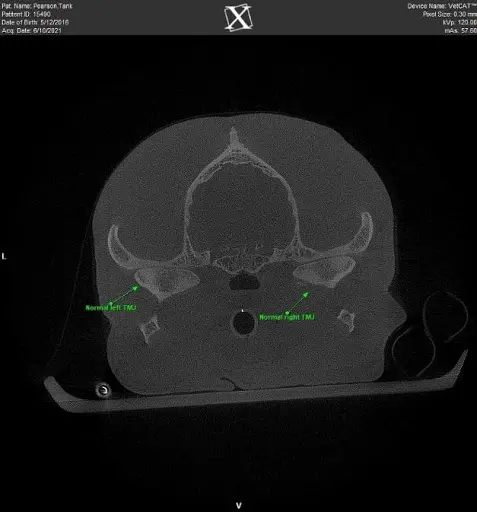

Figure 1 Cone Beam Computed Tomography image of normal TMJs in an adult dog

The temporomandibular joint is a “hinge” joint responsible for opening and closing the oral cavity. The TMJ movement differs across species due to each species’ dietary requirements. In dogs, TMJ movement involves flexion and extension with minor translational movement.

Anatomically, the condylar process of each mandible articulates with the mandibular fossa of the temporal bone. A fibrocartilaginous disc provides a cushion at the joint surfaces. The TMJ in dogs plays a role in occlusion (or the way teeth meet) and is prone to developmental, traumatic, and age-related diseases.

TMJ disease is diagnosed most accurately through imaging. Skull radiographs are beneficial but often are challenging to interpret as they are two-dimensional images. Cone-beam CT imaging provides 3-D evaluation and is invaluable for diagnosing TMJ disorders. This imaging modality is completed under general anesthesia, with imaging results in less than 4 minutes in most patients.